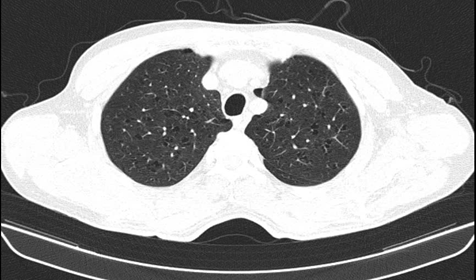

– Chụp Cắt lớp vi tính lồng ngực: Hình ảnh nốt đặc thùy trên phổi trái và thùy giữa phổi phải. Nốt vôi hóa thùy dưới phổi phải. Chưa phát hiện tổn thương ác tính

Phim chụp cắt lớp vi tính lồng ngực